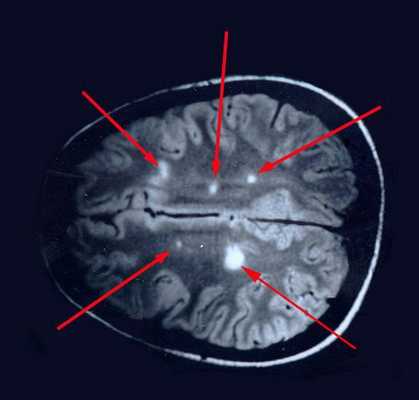

МРТ — магнитно-резонансная томография

На МРТ, в отличие от других лучевых исследований, очень хорошо видно структуру и вещество мозга. Это важно при изучении поражения процессом рассеянного склероза. Современным стандартом является МРТ с контрастом с препаратом гадолиния.

- Локализировать очаги воспаления

- Определить стадию

- Контролировать тяжесть процесса.

Поставить диагноз по данным МРТ в отрыве от клинической картины невозможно, так как изменения в веществе головного мозга не всегда связаны с рассеянным склерозом.

При вероятном РС, наряду с полным неврологическим осмотром, необходимо проводить исследование головного и спинного мозга при помощи МРТ. Этот способ исследования является наиболее информативным дополнительным методом диагностики. С его помощью можно обнаружить участки изменённой плотности в белом веществе головного мозга (очаги демиелинизации и глиоз). [10]

![МРТ мозга]()